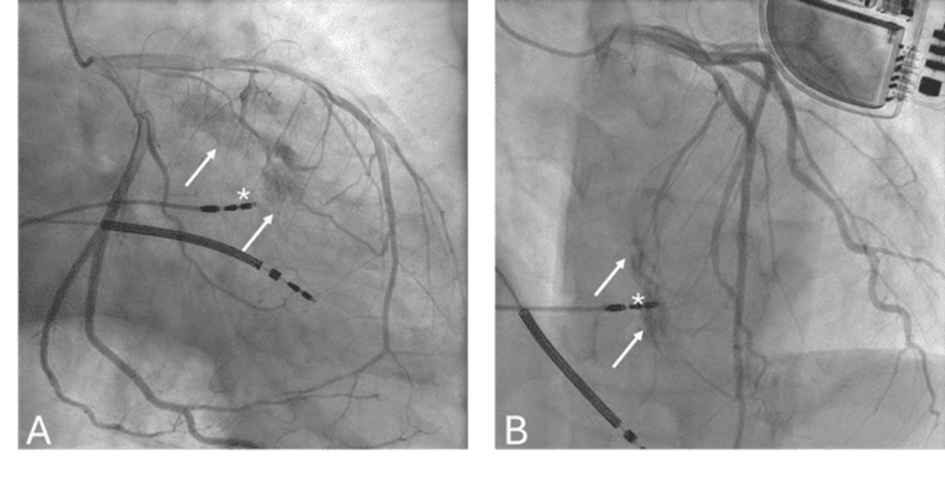

Coronary angiography (Figure) demonstrated contrast extravasation (Videos 1 and 2) from a large septal branch of the left anterior descending coronary artery toward the right ventricle. Given the small shunt and the asymptomatic presentation, a conservative management strategy was adopted.